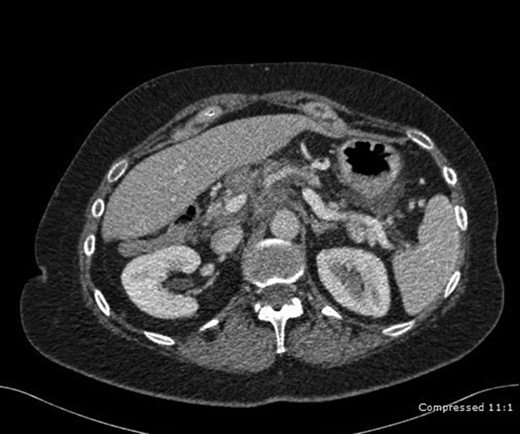

A 62-year-old female with history of Crohn’s was referred to our hospital with abdominal pain that started 5 months ago accompanied by nausea and vomiting. Review of systems was negative for weight loss or loss of appetite. She had no previous history of pancreatitis or family history of pancreatic cancer. The patient’s complete blood count and comprehensive metabolic panel were within normal limits. Her Ig G and ANCA levels were normal, thus ruling out autoimmune pancreatitis. CT revealed a diffuse tissue mass in the head and tail of the pancreas (Fig. 2). Fine needle aspiration of the mass through endoscopic ultrasound yielded only chronic inflammatory cells (lymphocytes, lymphocytic aggregates, macrophages, lympho histiocytic aggregates). A CT-guided percutaneous FNA of a peripancreatic lymph node also revealed no evidence of malignancy.

CT abdomen depicting a diffuse tissue mass in the head and tail of the pancreas.